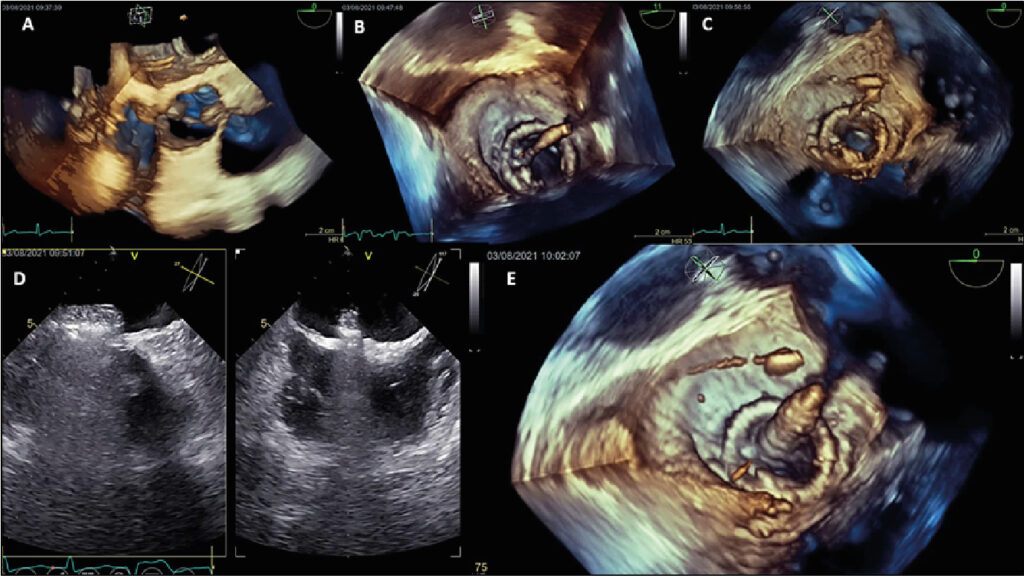

My Approach to Transseptal Mitral Valve-In-Valve

The first valve-in-valve (VIV) procedures were performed to treat deteriorated bioprosthetic valves in the aortic position. , In 2009, the group led by Dr. John Webb published the first successful case of mitral VIV. Since then, mitral VIV has been performed in numerous centers worldwide.